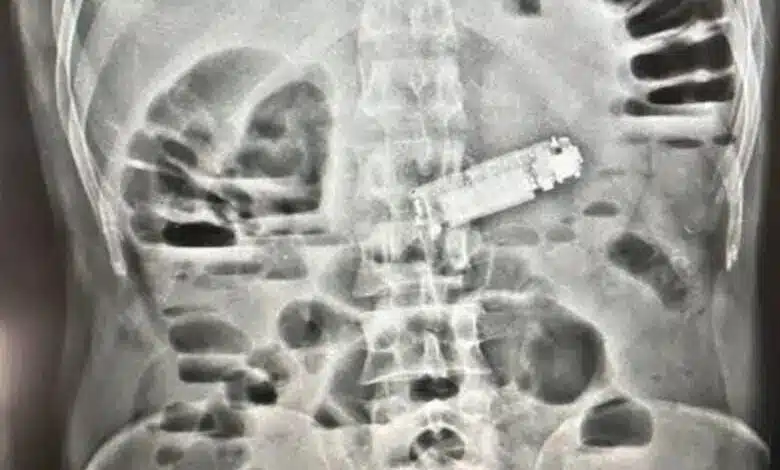

أجرى الفريق الطبي للمريض كافة الفحوصات اللازمة والأشعة التشخيصية، التي أظهرت وجود جسم غريب يعيق عمل المعدة، ليتبين أنه هاتف محمول تسبب في انسداد فتحة البواب، وهو ما كان وراء الأعراض الخطيرة التي يعاني منها المريض